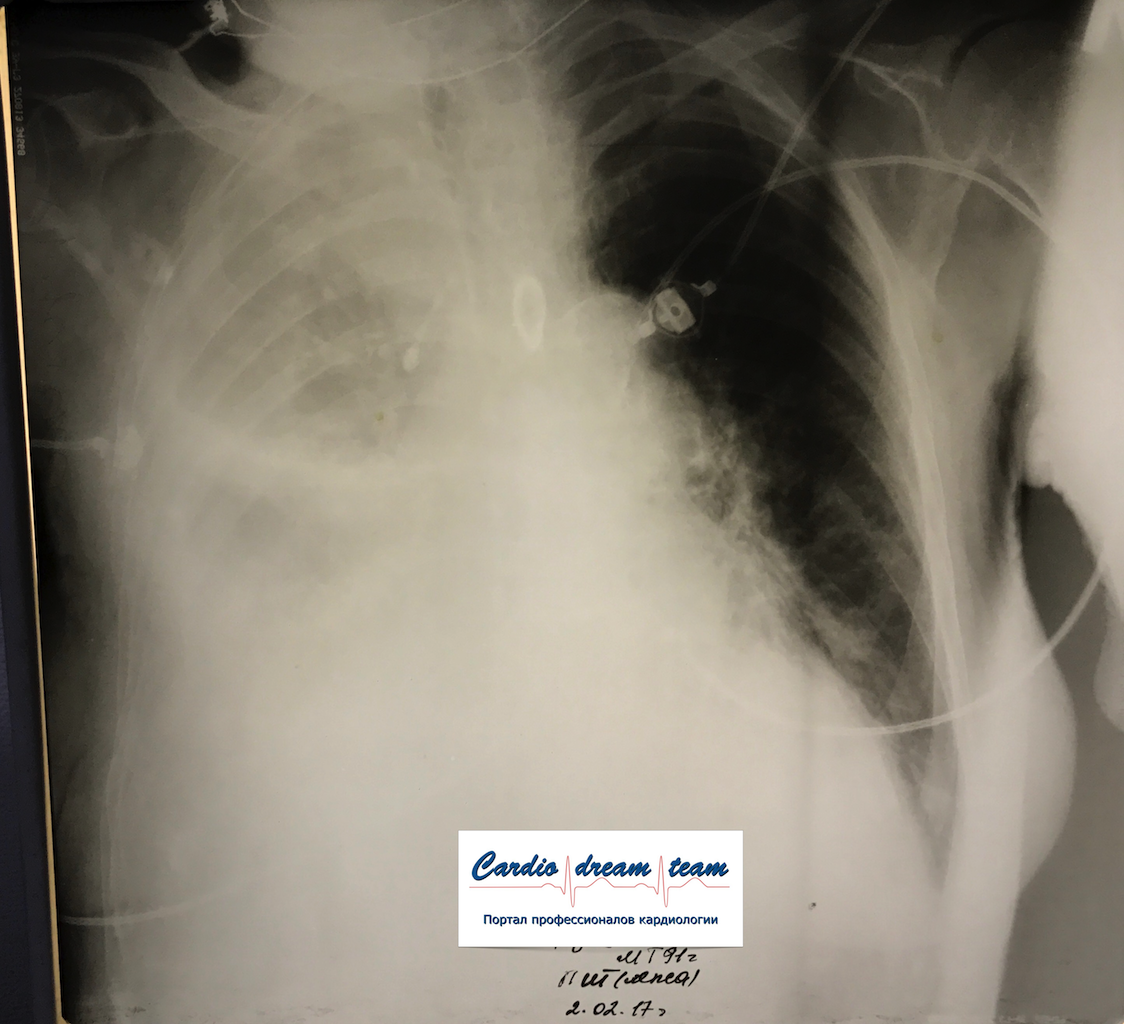

Гидроторакс. Серия снимков.

1 - лежа. Так делать не надо! Надо только сидя!

2 - сидя. Понятно, что гидроторакс за раз не победить

3 - удалено 1100.

4 - удалено ещё 1200. И диуретики все эти дни.